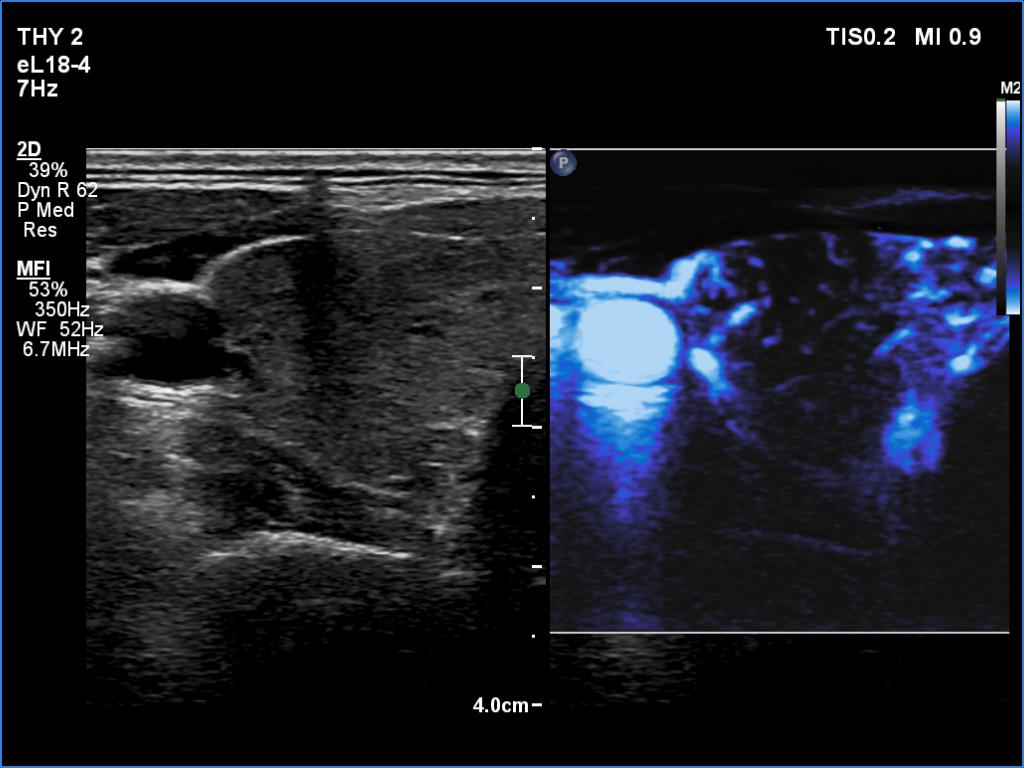

Right lobe, microflow imaging

Left lobe, microflow imaging